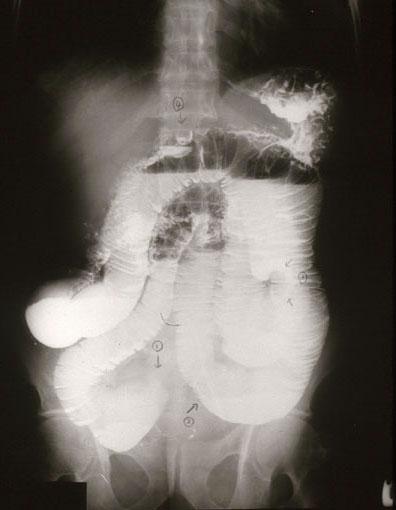

疾患(病理主体)の分類転移性腫瘍/

部位(臓器別)小腸/空腸

検査方法X-P

病変の最大径(ミリ)30〜34

多発腫瘍(同一臓器)有(同時性)

多重腫瘍(他臓器)有(同時性)